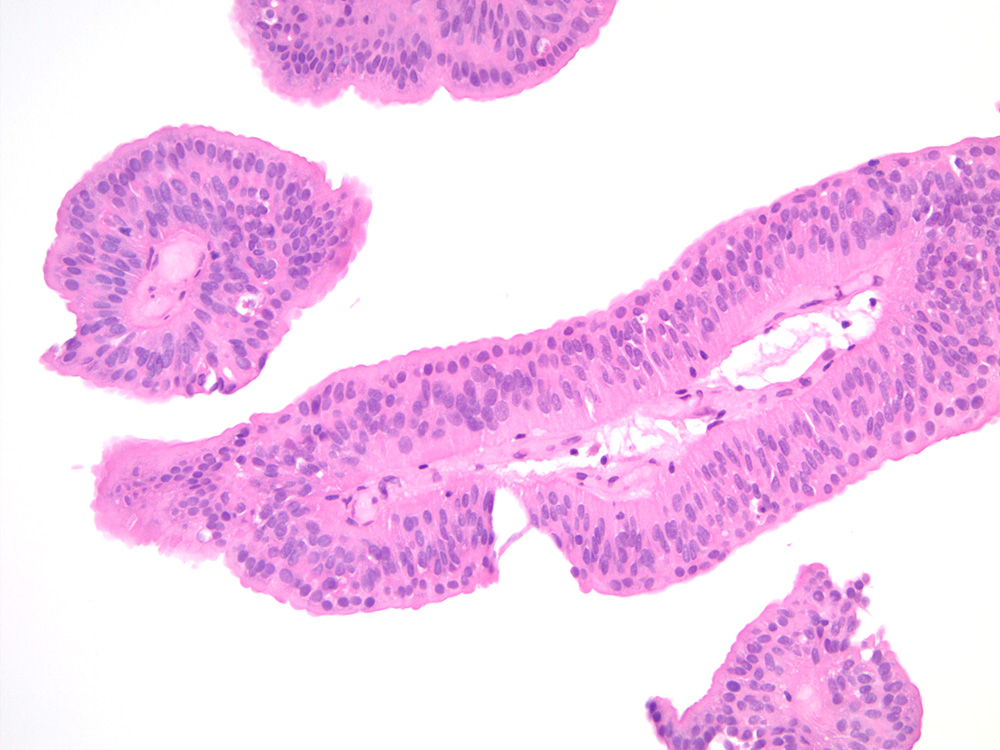

Consensus grade: Papilloma

Small papillary lesion in urinary bladder